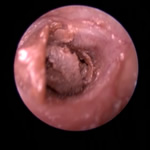

ポリープや腫瘤を伴う耳道炎と中耳炎

外耳炎が慢性化すると過形成、アポクリン腺腫瘍、炎症性ポリープ、鼻咽頭ポリープ(猫)などにより耳道が狭くなったり、閉塞することがあります。これが原因で外耳炎が治癒せず中耳炎に至るケースがよくあります。この状態になると生涯にわたり治療が必要になったり、根治には手術が必要になることもあります。